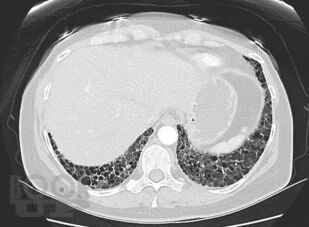

В учебном пособии рассматриваются актуальные и современные вопросы диагностики и лечения интерстициальных заболеваний легких.